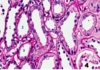

What do you see here?

Acute interstitial nephritis